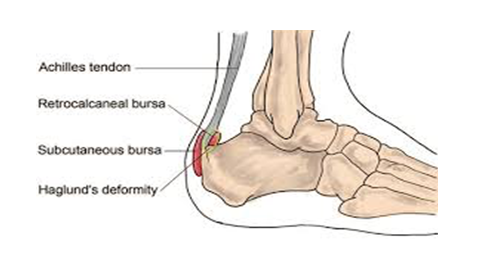

Really painful heel top, Posterior heel pain Chelsea and Westminster Hospital NHS top

Posterior heel pain Chelsea and Westminster Hospital NHS